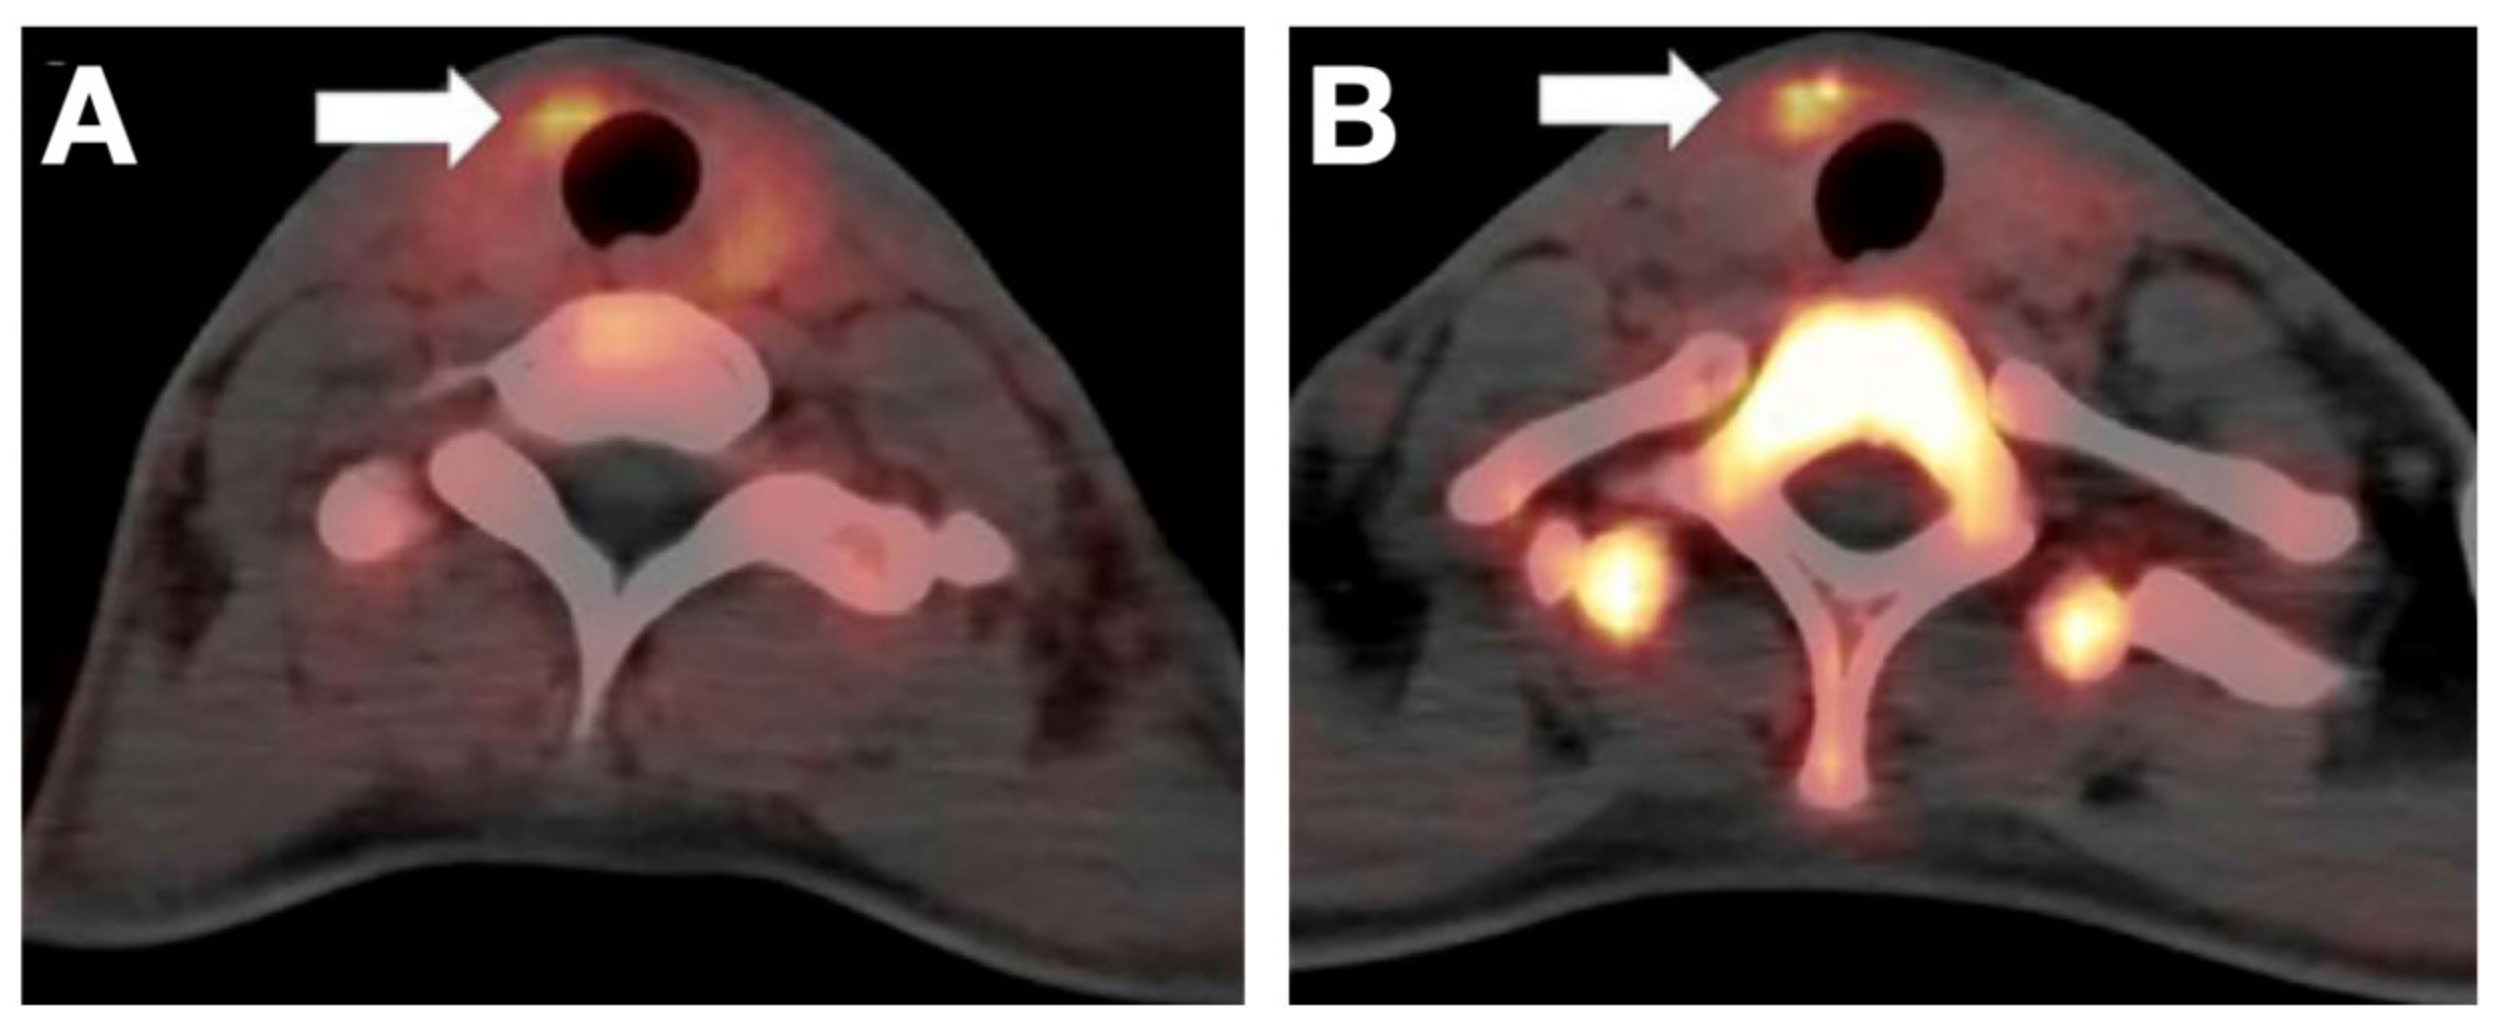

- Wei, W.; Jiang, D.; Rosenkrans, Z.T.; Barnhart, T.E.; Engle, J.W.; Luo, Q.; Cai, W. HER2-Targeted Multimodal Imaging of Anaplastic Thyroid Cancer. Am. J. Cancer Res. 2019, 9, 2413–2427. [Google Scholar]